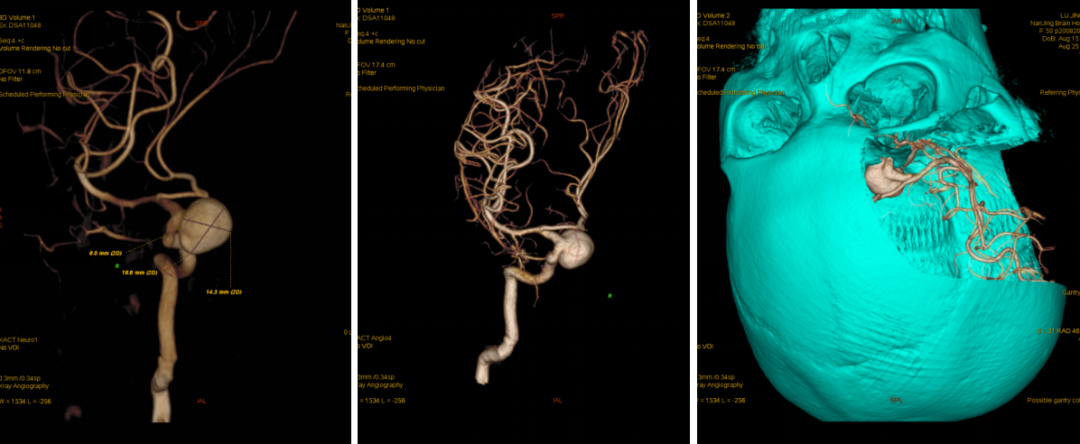

今日与大家分享的是《正海-妙术视界》第二百三十三期,由南京脑科医院何升学主任医师带来的Dolenc入路和颈部颈动脉逆向抽吸技术处理床突旁大动脉瘤2例,欢迎观看、分享。

入院后予完善MRI及头颅DSA检查提示右侧颈内动脉眼动脉段动脉瘤;告知其介入栓塞、开颅夹闭等治疗方式、利弊、风险及费用等,患方商量后决定行开颅动脉瘤夹闭术。

科内讨论后认为:患者颈内动脉床突旁大动脉瘤诊断明确,患者动脉瘤破裂出血,需急诊手术治疗。术中应先在颈部暴露颈内动脉。采用Dolenc入路硬膜外磨除前床突及视神经管。术中注意保护好眼动脉。暴露动脉瘤后可孤立动脉瘤,并在颈部穿刺颈动脉并逆向抽吸,降低动脉瘤的张力后塑形夹闭动脉瘤。

头颈部CTA

术前DSA